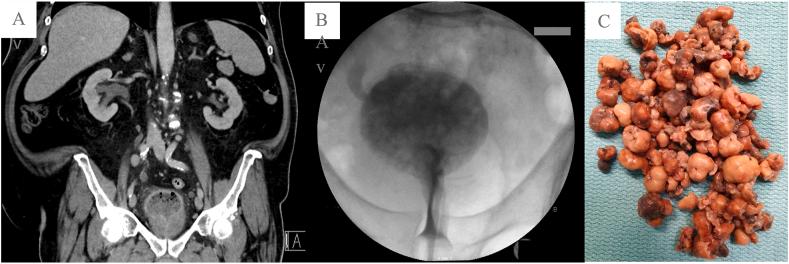

Fungus formation in the urinary tract mainly occurs in immunosuppressed patients, and is a rare and dangerous complication of candiduria that is commonly misdiagnosed. We report a case of intravesical mycetoma associated with hydronephrosis, initially diagnosed as enterovesical fistula. Cystoscopy revealed spongy material within the urinary bladder, and histopathological examination showed Mycetoma of Candida species. The urine culture showed . Endoscopic removal and antifungal therapy with fluconazole was initiated, and no complications occurred during follow-up.

真菌在泌尿道形成主要发生在免疫抑制患者中,是念珠菌尿症一种罕见且危险的并发症,常被误诊。我们报告一例与肾积水相关的膀胱内足菌肿病例,最初被诊断为肠膀胱瘘。膀胱镜检查发现膀胱内有海绵状物质,组织病理学检查显示为念珠菌属足菌肿。尿液培养显示……开始进行内镜切除并使用氟康唑进行抗真菌治疗,随访期间未发生并发症。